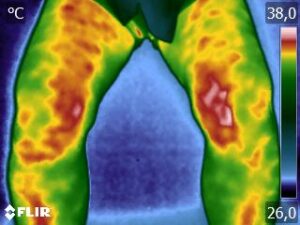

Como no caso da sequência de termogramas abaixo de uma paciente do sexo feminino, 42 anos, sem comorbidade e que apresentou dor em joelhos após treino de musculação. Foi realizado uma Análise Termofuncional e detectado alterações térmicas condizentes com o relato de dor.

Estas informações foram a oportunidade para convencer a paciente a realizar uma ressonância magnética para determinar o grau de comprometimento tecidual. Pois sem isso, após a melhora da dor, a liberação de carga e até a carga terapêutica ficariam limitadas.

Já com este conhecimento foi possível determinar um tratamento que abarcasse as áreas de dor e as áreas de comprometimento tecidual que apresentam inflamação, até a paciente retornar com o resultado da ressonância.

Isso adianta e muito a reabilitação, pois oferece informação que a olho nu não seria possível.